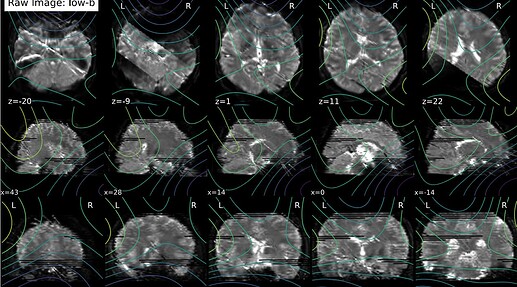

I’m using QSIprep 0.22.0 for preprocessing a dMRI dataset. For two subjects, the preprocessed data seem stripped -but not as the whole slices are missing- evident as early as in the denoising report:

The raw data has no evident issues. I repeated the analysis with QSIprep 1.0.2; the issue remained, but different slices were missing.